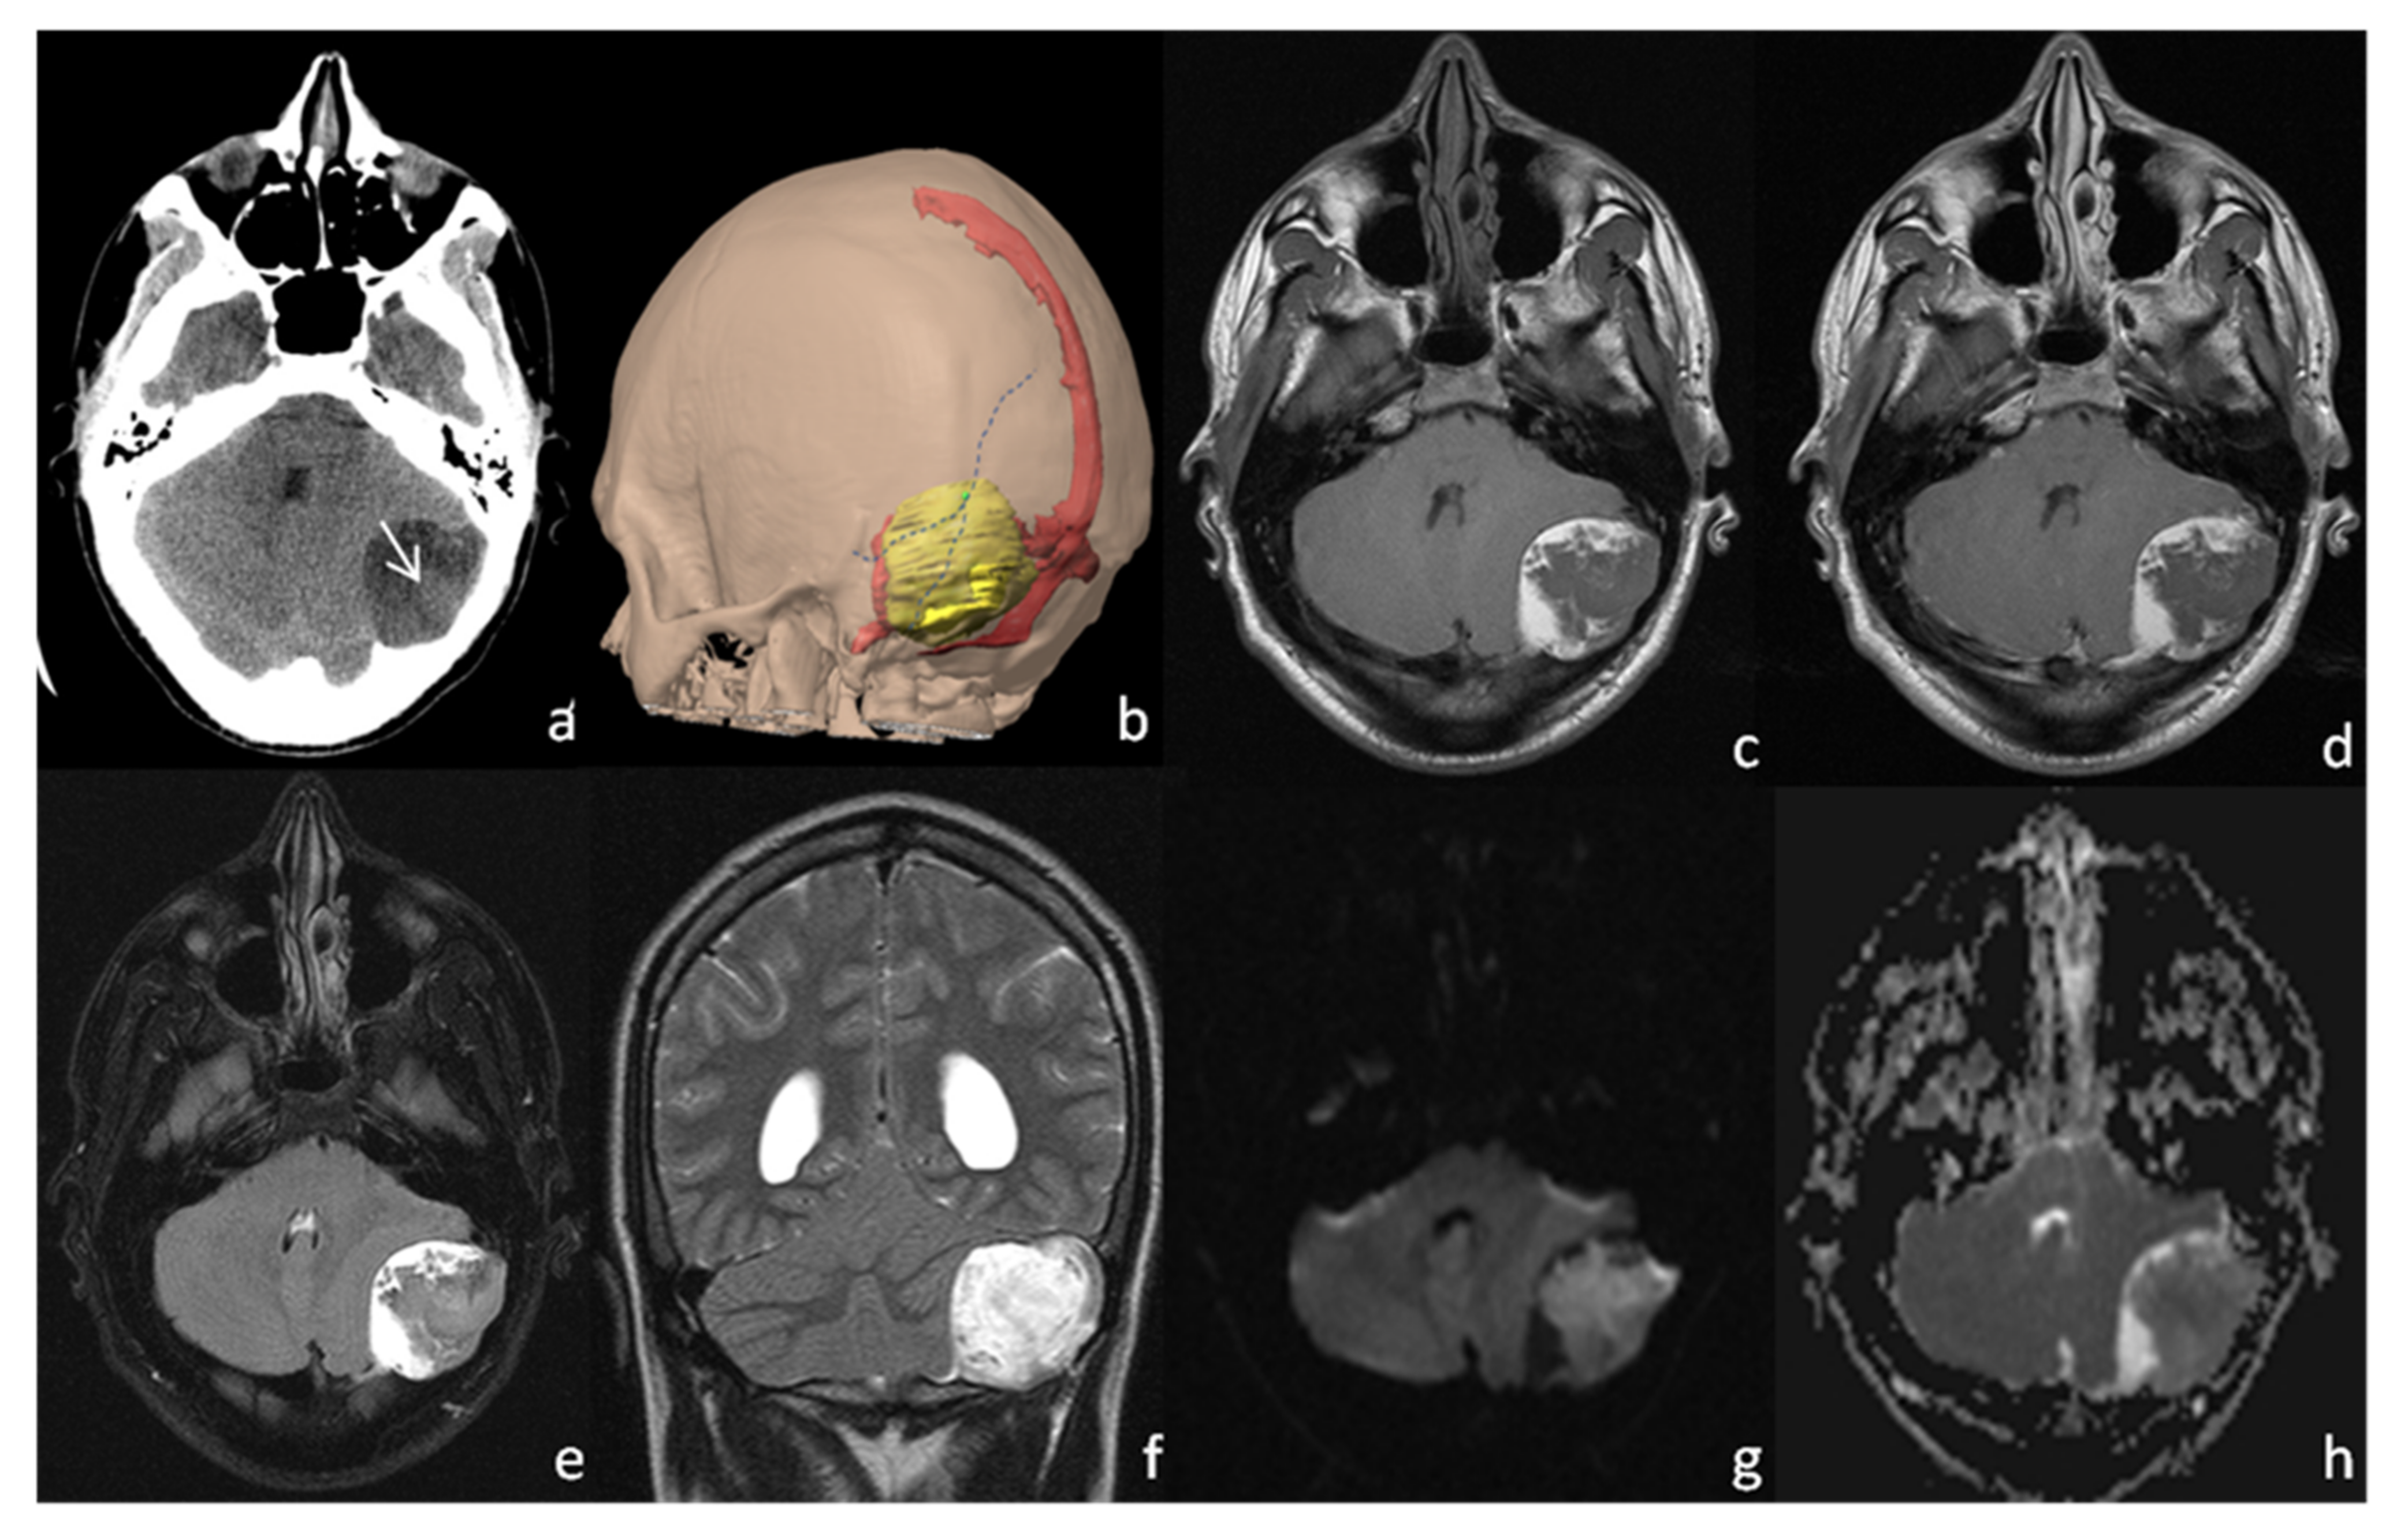

2. Case Presentation